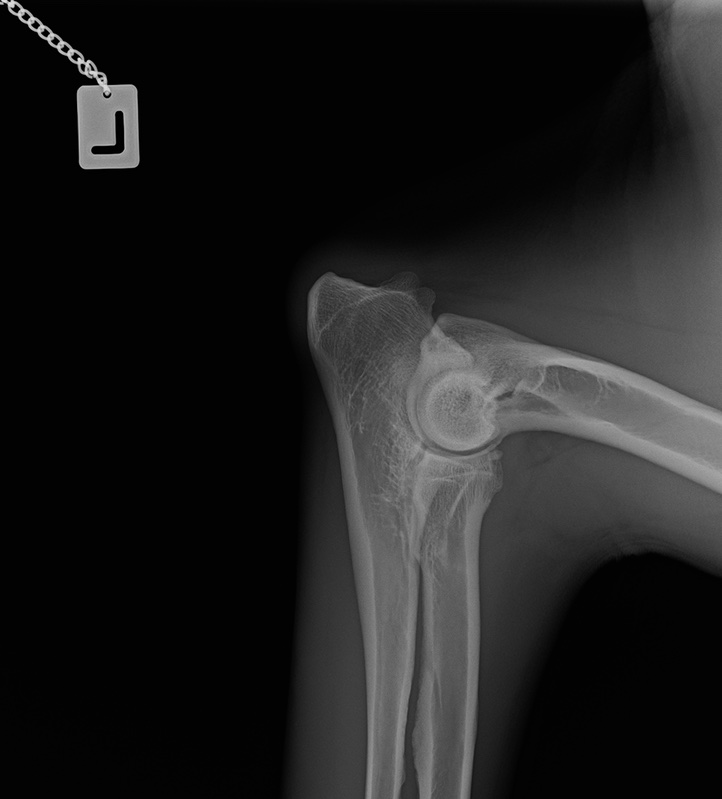

Wir warten jetzt mal die offizielle Auswertung ab. Bin auch gespannt, was nun bei OCD und Lendenübergangswirbel rauskommt. Und welcher LÜW-Typ.

Das ist ganz einfach. Man schreibt ne Email, bittet um ein Privatgutachten und schickt ihm die Röntgenbilder.

Das Ergebnis + Rechnung kommt echt schnell ( 1-2 Tage)